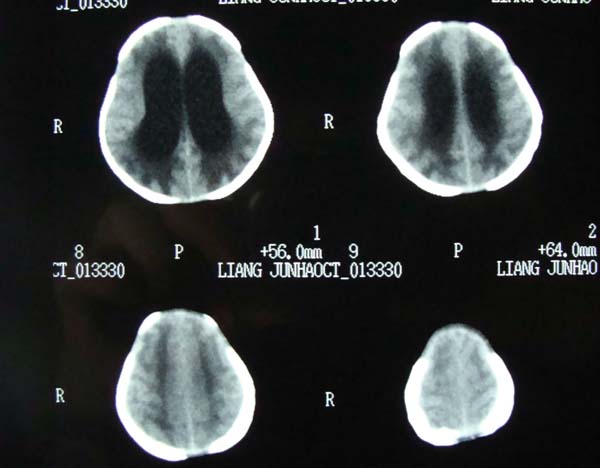

病史,xxx,男,10个月,前囟饱满.呕吐.

考虑第四脑室室管膜瘤并阻塞性脑积水。

小脑蚓部髓母细胞瘤?第四脑室室管膜瘤?合并重度阻塞性脑积水。

考虑第四脑室室管膜瘤并阻塞性脑积水

考虑第四脑室室管膜瘤或髓母细胞瘤并阻塞性脑积水。

诊断:髓母细胞瘤并梗阻性脑积水.

依椐:颅后窝中线小脑蚓部占位,病灶内呈混杂密度,四脑室受压前移,第三脑室及侧脑室扩张.